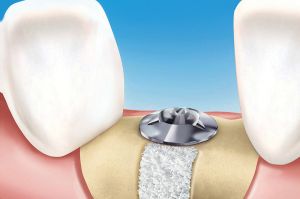

Darstellung des Knochenaufbauverfahrens

Sinuslift – Eine besondere Art des Knochenaufbaus

Im Oberkiefer-Seitenzahnbereich führt die große luftgefüllte Kieferhöhle oft zu einem unzureichenden vertikalen Knochenangebot, was eine einfache Implantation in diesem Bereich häufig unmöglich macht. Hier schafft ein Knochenaufbau nach dem Sinuslift-Verfahren Abhilfe.

Über einen operativen Zugang vom Munde her wird der Kieferhöhlenboden dargestellt und die bedeckende Schleimhautmembran vorsichtig angehoben. Der entstehende Hohlraum wird mit Eigenknochen-Granulat und/oder Knochenersatzmaterial aufgefüllt. Ist noch eine gewisse Höhe an Eigenknochen vorhanden, so können die Implantate zeitgleich mit der Sinusliftoperation eingebracht werden. Bei sehr geringem Knochenangebot wird zunächst nur der Knochen aufgebaut und sechs Monate danach in den aufgebauten Knochen implantiert.